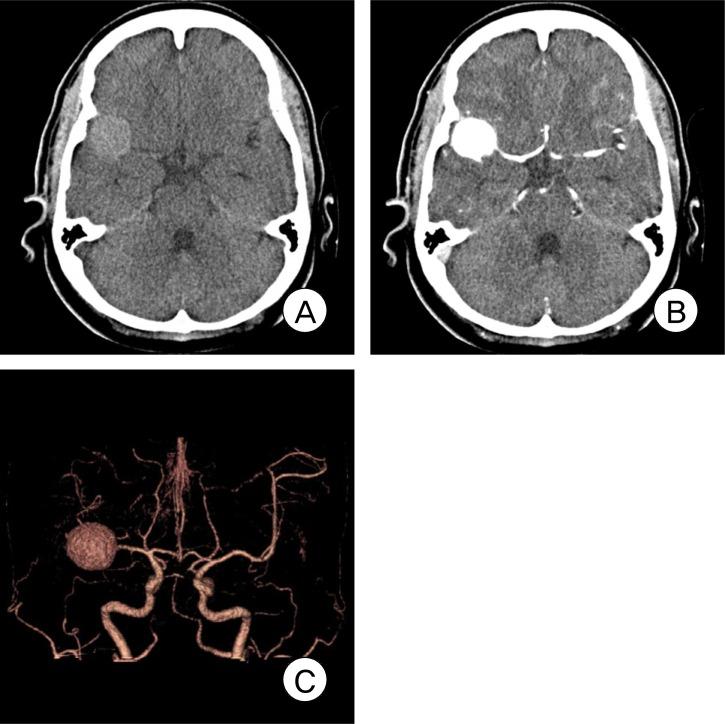

There are few observation papers regarding the natural history of an aneurysm. We report on a case of a completely occluded middle cerebral artery (MCA) aneurysm. A 47-year-old female patient presented with a headache and was diagnosed with rupture of a right MCA aneurysm. Due to a high risk of direct neck clipping, she received conservative treatment after craniotomy and wrapping of her aneurysm. The patient's condition showed improvement, with complete occlusion of the aneurysm and considerable reduction of the aneurysm in size after approximately three years. This is a rare case of an aneurysm of MCA that showed spontaneous resolution. Finally, on the angiogram, characteristics of an aneurysm to occlude spontaneously will be presumed based on literature reviews.

关于动脉瘤自然史的观察性论文很少。我们报告一例大脑中动脉(MCA)动脉瘤完全闭塞的病例。一名47岁女性患者因头痛就诊,被诊断为右侧MCA动脉瘤破裂。由于直接夹闭颈部的风险较高,她在开颅手术和包裹动脉瘤后接受了保守治疗。大约三年后,患者病情有所改善,动脉瘤完全闭塞且大小显著缩小。这是一例罕见的MCA动脉瘤自发消退病例。最后,基于文献综述,在血管造影上推测动脉瘤自发闭塞的特征。